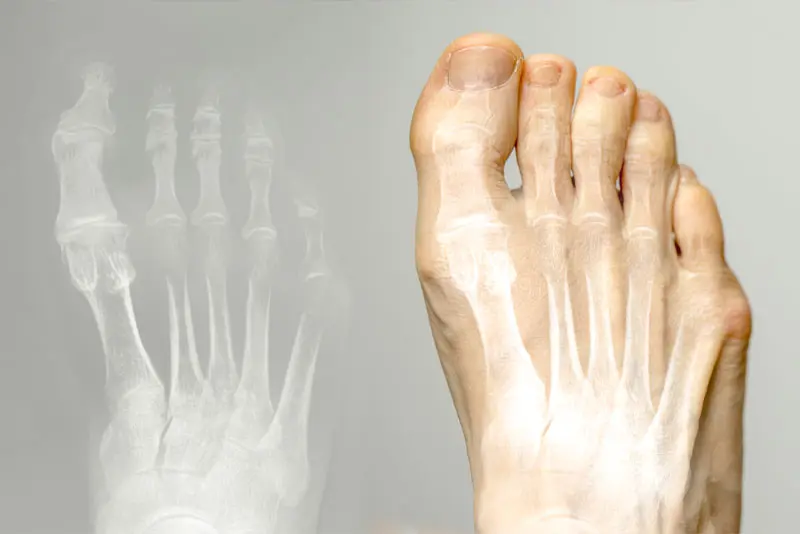

Bunion (Hallux Valgus) - Minimally Invasive Surgical Correction

More than one third of people over the age of 65 have bunions. It affects ladies twice as much as men. Many people live with this condition without any trouble. For many others however this stubborn lump on the inner side of the foot creates significant problem when shoes become more and more difficult to ware, and the big to continues to progressively drift laterally causing lesser toes deformities, forming painful callosities and drastically reducing quality of life. For these patients a corrective surgery is the only reliable option.

I correct bunions through minimally invasive surgery. It means cutting and resetting bones in the foot through tiny skin incisions using special instruments and implants. With minimal soft tissue trauma, and swelling this technique dramatically reduces pain and speeds up the recovery.

Bunion also called Hallux Valgus is a condition where the big toe over time gradually deviates outwards. This may lead to prominent bony bump with persistent throbbing pain over the inner side of the foot as well as great difficulty wearing shoes. Also, the big toe can encroach on neighbouring 2nd toe and make it to go either over or under it with crowding of other lesser toes. Typically, the condition progresses gradually sometimes making it nearly impossible to wear normal shoes.

Although occasionally splints helping to realign the big toe better can alleviate the discomfort to some extent, as a rule this condition is likely to progress, and the surgical correction is required to sort out the problem.